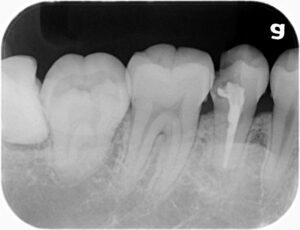

(12/01) <レントゲンでわかること>